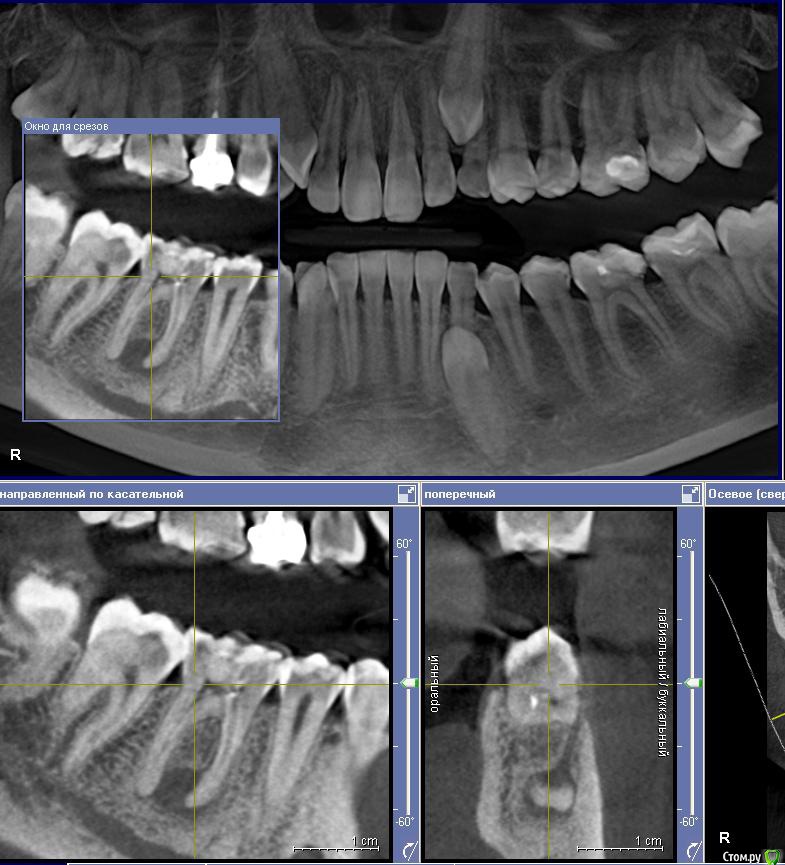

Ксения_ Опубликовано 27 августа, 2015 Поделиться Опубликовано 27 августа, 2015 (изменено) Здравствуйте Уважаемые Доктора! КТ сделано 4 мес назад. После этого пролечен кариес 14, 16, 37, 35. Пролечен пульпит 25, 36.Осталось пролечить пульпит в 15, 26, 47. Удалить все восьмерки.Далее ортодонтия. Стоит вопрос об удалении 46. Зуб ранее был пролечен другим врачом некачественно (+ пропущен канал).Мой лечащий доктор, после консультаций с коллегами, предлагает удаление, т.к. с его слов прогноз у этого зуба неблагоприятный (считает, что через пару лет процесс повторится) и смысла в столь дорогом лечении нет. Мне, конечно, хотелось бы по возможности зуб сохранить.Как вы считаете какой прогноз у этого зуба? P.S. Зуб не беспокоит. Точнее ни один зуб у меня вообще ни разу в жизни не болел (несмотря на такое количество пульпитов, которые для меня были неожиданностью. Врачу своему доверяю.). Несколько докторов которые меня смотрели считают, что у меня высокий болевой порог. Изменено 27 августа, 2015 пользователем Ксения_ Ссылка на комментарий

M@estro Опубликовано 27 августа, 2015 Поделиться Опубликовано 27 августа, 2015 (изменено) Судя по рентгену - прогноз благоприятный. Зуб сохранен,это главное. "процесс повторится" - на это при современном подходе выделяют не более 5 % .Если бы у меня 95 % вероятности в казино было - я бы дом поставил , не то что зуб полечил ) Ключевое при перелечивании - соблюдение современного протокола лечения. P.s. После лечения уже больше двух лет прошло,недавно был на осмотре - процесс все никак не повторится )) Изменено 27 августа, 2015 пользователем M@estro 3 Ссылка на комментарий